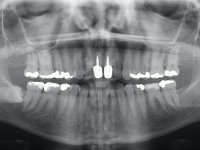

Paciente do sexo feminino com 41 anos de idade, não fumadora. Apresentava duas coroas sobre espigões falsos cotos fundidos nos dentes 1.1 e 2.1. As coroas apresentavam-se com infiltrações cervicais com exposição da superfície radicular. A papila gengival mediana, apresentava-se ligeiramente retraída. O espaço mesio-distal correspondente às duas coroas mostrava-se alto e estreito. Apresentava um ligeiro apinhamento dos incisivos inferiores, bem como uma pequena retração gengival. No sorriso era bem visível a zona cervical das coroas, mostrando um aspeto acinzentado correspondendo ao escurecimento radicular. No exame imagiológico verificou-se que o tratamento endodôntico não estava tecnicamente satisfatório, mas assintomático à quase 10 anos.

Foi proposta a substituição das duas coroas dos espigões falsos cotos fundidos após a realização de um branqueamento dentário. Equacionou-se também a possibilidade de refazer os tratamentos endodônticos, mas conclui-se que a remoção dos espigões falsos cotos teria um risco muito alto. Assim o plano de tratamento proposto resumiu-se à realização de um branqueamento dentário em ambulatório e à colocação de duas coroas com infraestrutura em Zr revestidas a cerâmica nos dentes 1,1 e 2.1.

O tratamento iniciou-se com a confeção de moldeiras transparentes em silicone para aplicação de peróxido de carbamida a 16%. Os espaçadores colocados na superfície vestibular foram cuidadosamente preparados em resina nos modelos de gesso. O tratamento foi feito aplicando o produto 2 horas por dia durante 8 dias. Após o branqueamento esperamos 4 semanas e iniciamos o tratamento prostodôntico. Foi realizada uma pré-impressão em silicone para confeção de uma ponte provisória com resina composta de polimerização dual. Em seguida iniciamos a remoção das coroas. Foi feito um corte vertical na zona média da coroa até encontrar a superfície do espigão falso coto fundido. No bordo incisal também foi realizado o mesmo corte. Em seguida com um luxador fino foi feita a separação das partes distais das coroas. Para a remoção das partes mesiais foi feito um corte na linha média abrangendo ambas as coroas. No final da remoção atraumática das coroas antigas os cotos foram re -preparados. Na re-preparação dos cotos a linha de acabamento foi colocada a nível intra-sulcular. Na mesma consulta foi feita a impressão definitiva. O afastamento gengival foi realizado com a técnica da pasta de caolino comprimida pela ponte provisória.  A impressão foi feita pela técnica de dupla mistura com dupla viscosidade com silicone de presa rápida. No laboratório foram confecionadas 2 coroas com infraestrutura em Zr sendo revestidas a cerâmica. No sentido de evitar aparência de coroas “muito altas” foi aumentado ligeiramente o diâmetro mesio-distal sobrepondo-se ligeiramente aos dentes adjacentes. A ponte provisória foi removida os cotos foram polidos e as coroas foram colocadas para verificação final. Confirmado o seu ajuste e aprovadas pela paciente foram cimentadas definitivamente com cimento de ionómero de vidro reforçado com resina.